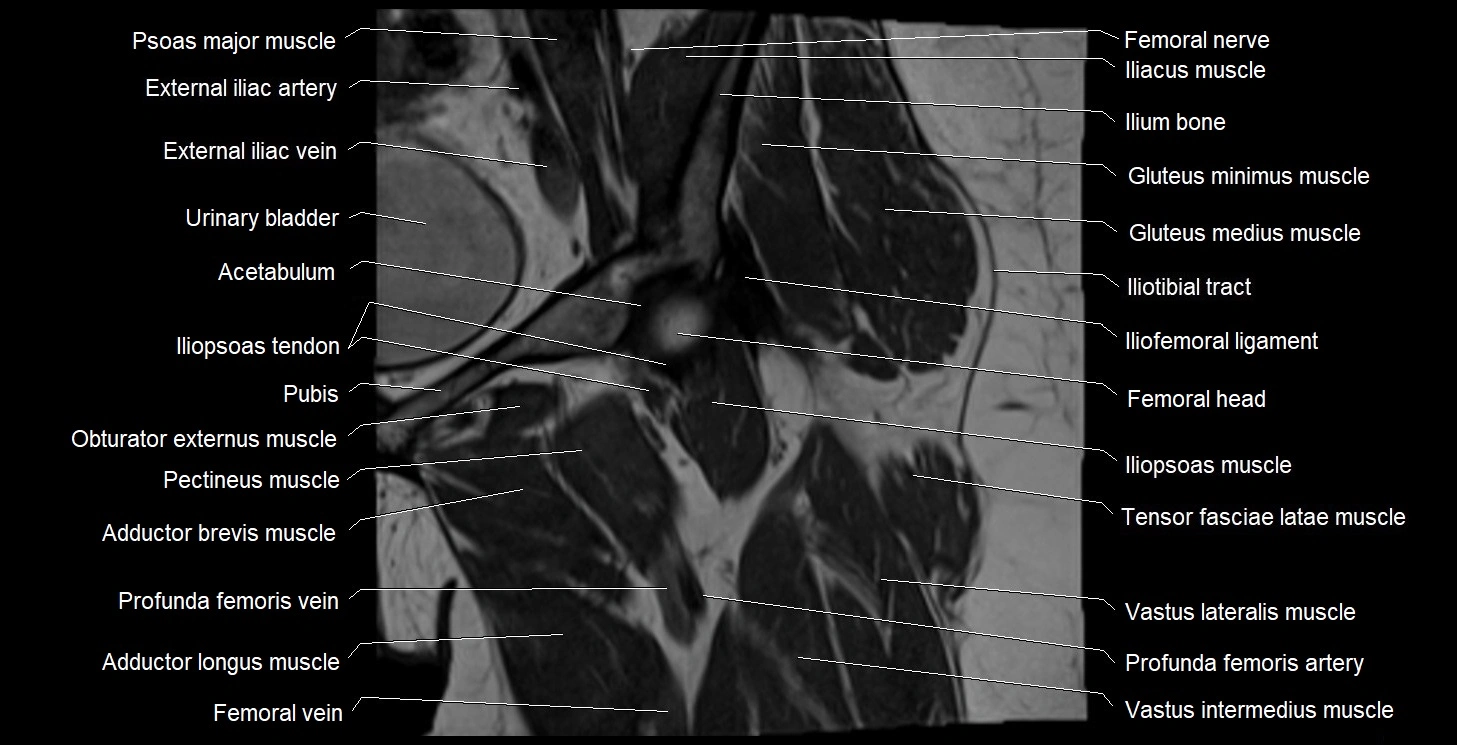

- Acetabulum

- External iliac artery

- External iliac vein

- Femoral nerve

- Femoral vein

- Gluteus medius muscle

- Gluteus minimus muscle

- Head of femur

- Iliofemoral ligament

- Iliopsoas muscle

- Iliopsoas tendon

- Iliotibial tract

- Ilium bone

- Obturator externus muscle

- Pectineus muscle

- Psoas major muscle

- Tensor fasciae latae muscle

- Urinary bladder

- Vastus intermedius muscle

- Vastus lateralis muscle